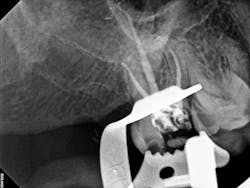

In the case below, tooth No. 2 was diagnosed with symptomatic irreversible pulpitis and symptomatic apical periodontitis with a mesial marginal ridge fracture due to extensive caries (figure 1). Root canal therapy and a full coverage crown were recommended and the patient accepted.